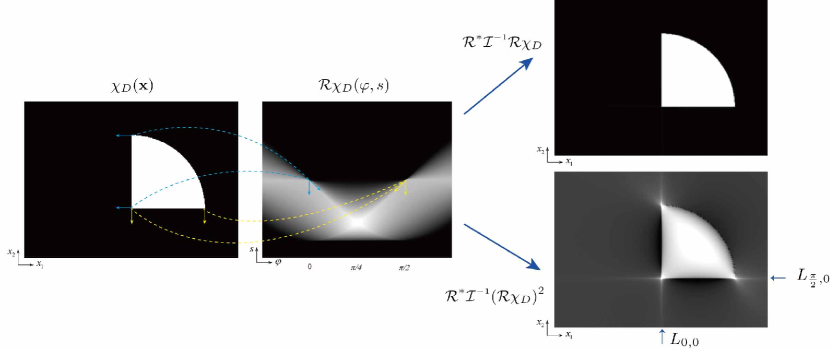

Fig. 3 illustrates how streaking artifacts are produced by the geometric structure of . In Fig. 3, is given by so that contains the line segments and . Using arguments in the proof of Theorem 3.1, we have

Hence, the lines and can be included in . Fig. 3 shows that the lines and are streaking artifacts.